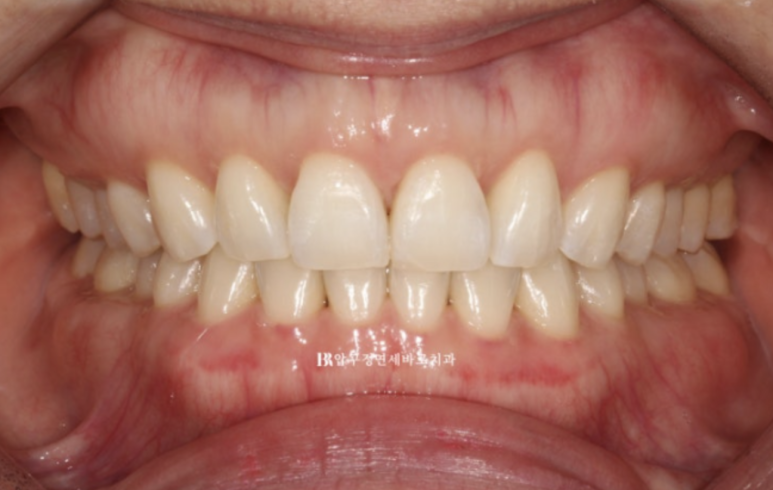

24.5

Q 인비절라인으로 교합이 제대로 맞지 않는다는 말이 사실인가요?

A. 이는 일부 오해입니다. 정확한 진단과 치료 계획, 그리고 필요 시 보조 장치 활용이 이루어진다면 인비절라인으로도 기능적으로 안정적인 교합을 충분히 만들 수 있습니다. 본 사례처럼 어금니 교합까지 안정적으로 마무리되는 결과도 많습니다.

가위교합이였던 우측 상악 제 2대구치 교합도 잘 유지가 되고 있습니다.

23.07~24.05

악궁 모양과 배열이 잘 잡혔고 재제작때 미니스크류 뺀 자리는 잘 안물어서 흔적이 없습니다.

흉터가 작게 남는 경우도 있지만 흉터도 남지 않는 경우가 많습니다.